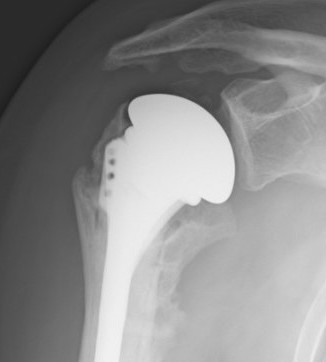

Reverse shoulder arthroplasty

Reverse

- socket in proximal humerus

- ball in glenoid

- center of rotation shifted medially and distally

- allows deltoid to apply compressive force and stabilize joint in absence of rotator cuff

Paul Grammont in 1985

- humeral component concave

- glenoid component / glenospere convex

- glenoid component uncemented with peripheral screws and central plug

- center of rotation shifted medially to glenosphere with humerus distal